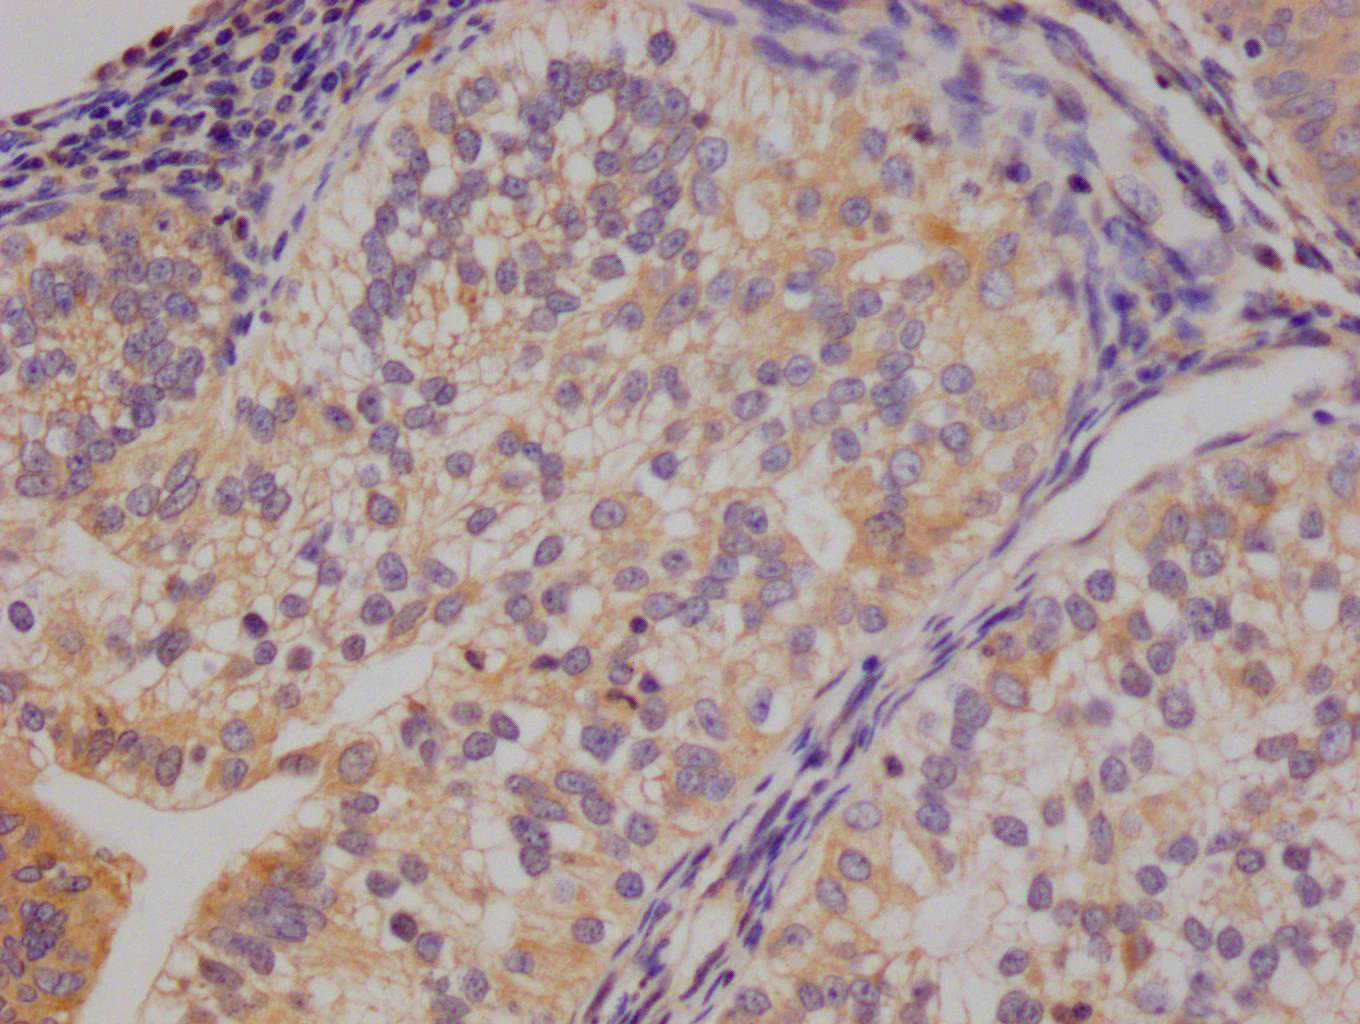

The image on the left is immunohistochemistry of paraffin-embedded Human breast cancer tissue using CSB-PA969280(IRS2 Antibody) at dilution 1/100, on the right is treated with synthetic peptide. (Original magnification: ×200)